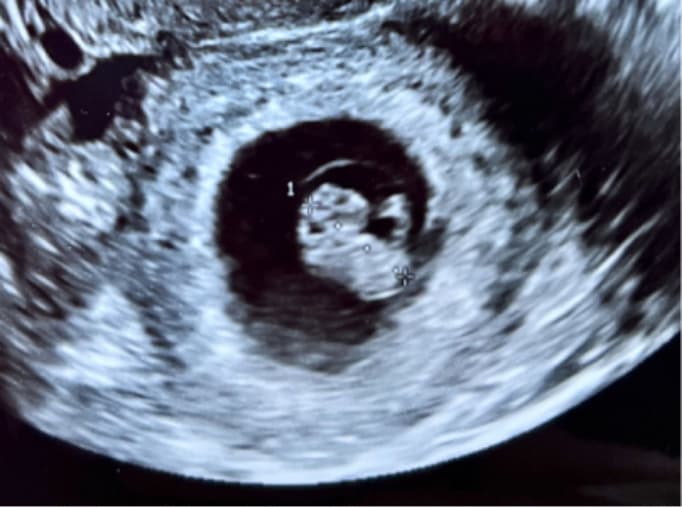

〜10週

健診頻度:1〜2週間毎

• 経膣エコーで子宮内の正常妊娠であるかを確認します。

• 流産兆候などの有無を調べます。

妊娠8 〜10週 頃で出産予定日を決定します。

赤ちゃんのサイズで予定日を確定します

胎児エコー写真

4D胎児エコー写真

(6週)